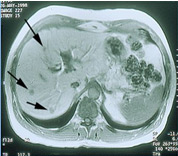

Ultrazvukové (sonografické) vyšetření jater: Jedná se o vyšetření, které doplňuje ostatní metody a umožňuje nám rozlišit útvary s obsahem tekutiny, nezhoubné nádory tvořené cévními strukturami, zánětlivá ložiska a podobně. Toto vyšetření je možno provádět i v průběhu samotného operačního výkonu na játrech, kdy sondu přikládáme přímo na povrch jater - rozliší přesný počet ložisek v jaterní tkáni, jejich velikost, ohraničení, vztah k cévním strukturám, což v určitých případech usnadňuje rozhodnutí o způsobu vedení operačního výkonu.

Obrázek 3: Ultrazvukový nález nádoru jater (označen šipkami)